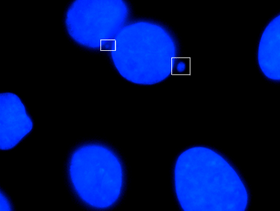

Cancerous micronuclei

Micronuclei are characterized in the cells that have some sort of DNA damage. This includes damage caused by radiation, harmful chemicals, and random mutations that occur throughout the genome. Micronuclei are small bodies that can be seen budding off of a newly divided daughter cell. Micronuclei can contain a whole chromosome or part of a chromatid. The increased formation of micronuclei is usually an indication of increased DNA damage or mutation. It is characteristically found in cancer cells, or cells that have been exposed to increased risk factors.

Micronuclei are often overlooked in cancer. If observed under a microscope, they are viewable and often next to other larger nuclei. Based on the structure of a Micronucleus, or the function of a cell, it provides support in the central apparatus within the cell. Micronuclei are under investigation and research regarding whether or not they can be used to predict future cancer risks. They are easy to analyze compared to chromosome aberrations.